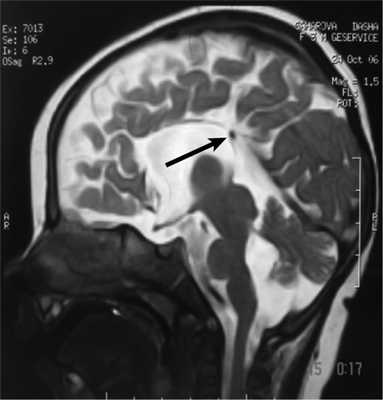

Рис. 3. МРТ головного мозга (сагиттальная проекция) больной С., 7 лет. АМТ (стрелка).

При МРТ мы обращали внимание также на описанное в литературе [12] изолированное расширение задних рогов — кольпоцефалию, обусловленную гипоплазией ассоциативных трактов белого вещества затылочных долей. Диагностический ряд на МРТ дополняют отсутствие нормально сформированных перикаллезных извилин (рис. 5, а) и радиальная центростремительная позиция борозд медиальной поверхности теменной доли (рис. 5, б).

Рис. 5. МРТ головного мозга больного А., 3 года. АМТ. а — сагиттальная проекция. Отсутствие нормально сформированных перикаллезных извилин (стрелка), б — высокое положение III желудочка, радиальная центростремительная направленность борозд медиальной поверхности теменных долей.